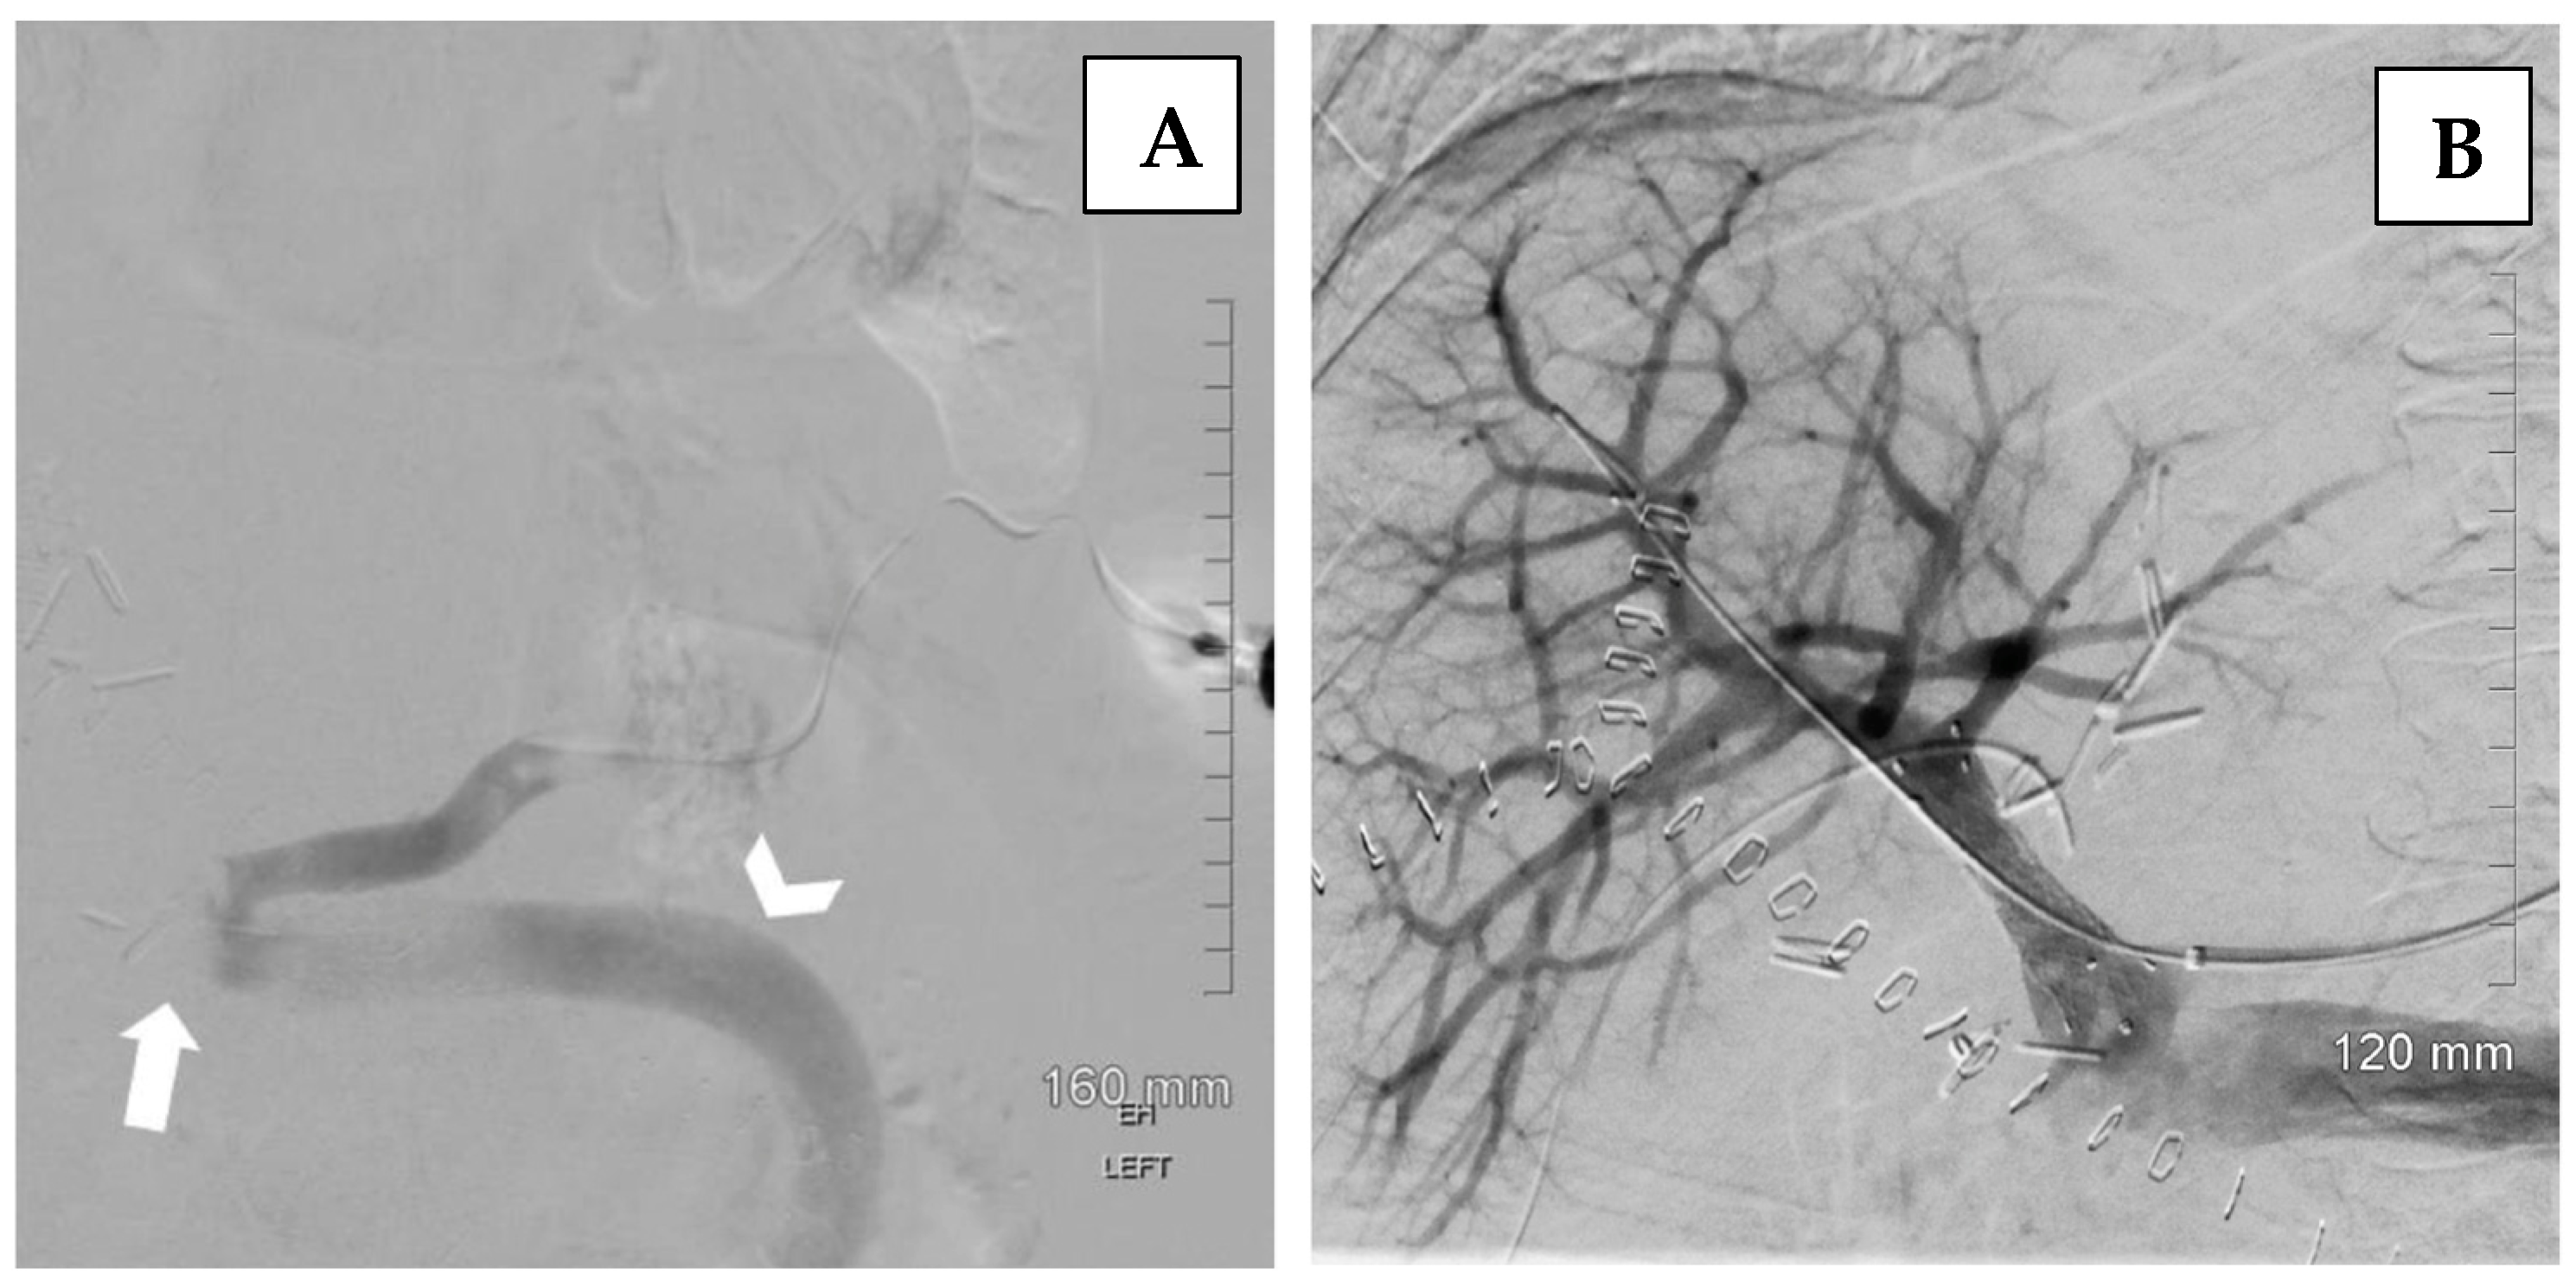

- Swersky, A.; Borja-Cacho, D.; Deitch, Z.; Thornburg, B.; Salem, R. Portal Vein Recanalization-Transjugular Intrahepatic Portosystemic Shunt (PVR-TIPS) Facilitates Liver Transplantation in Cirrhotic Patients with Occlusive Portal Vein Thrombosis. Semin. Intervent Radiol. 2023, 40, 38–43. [Google Scholar] [CrossRef]